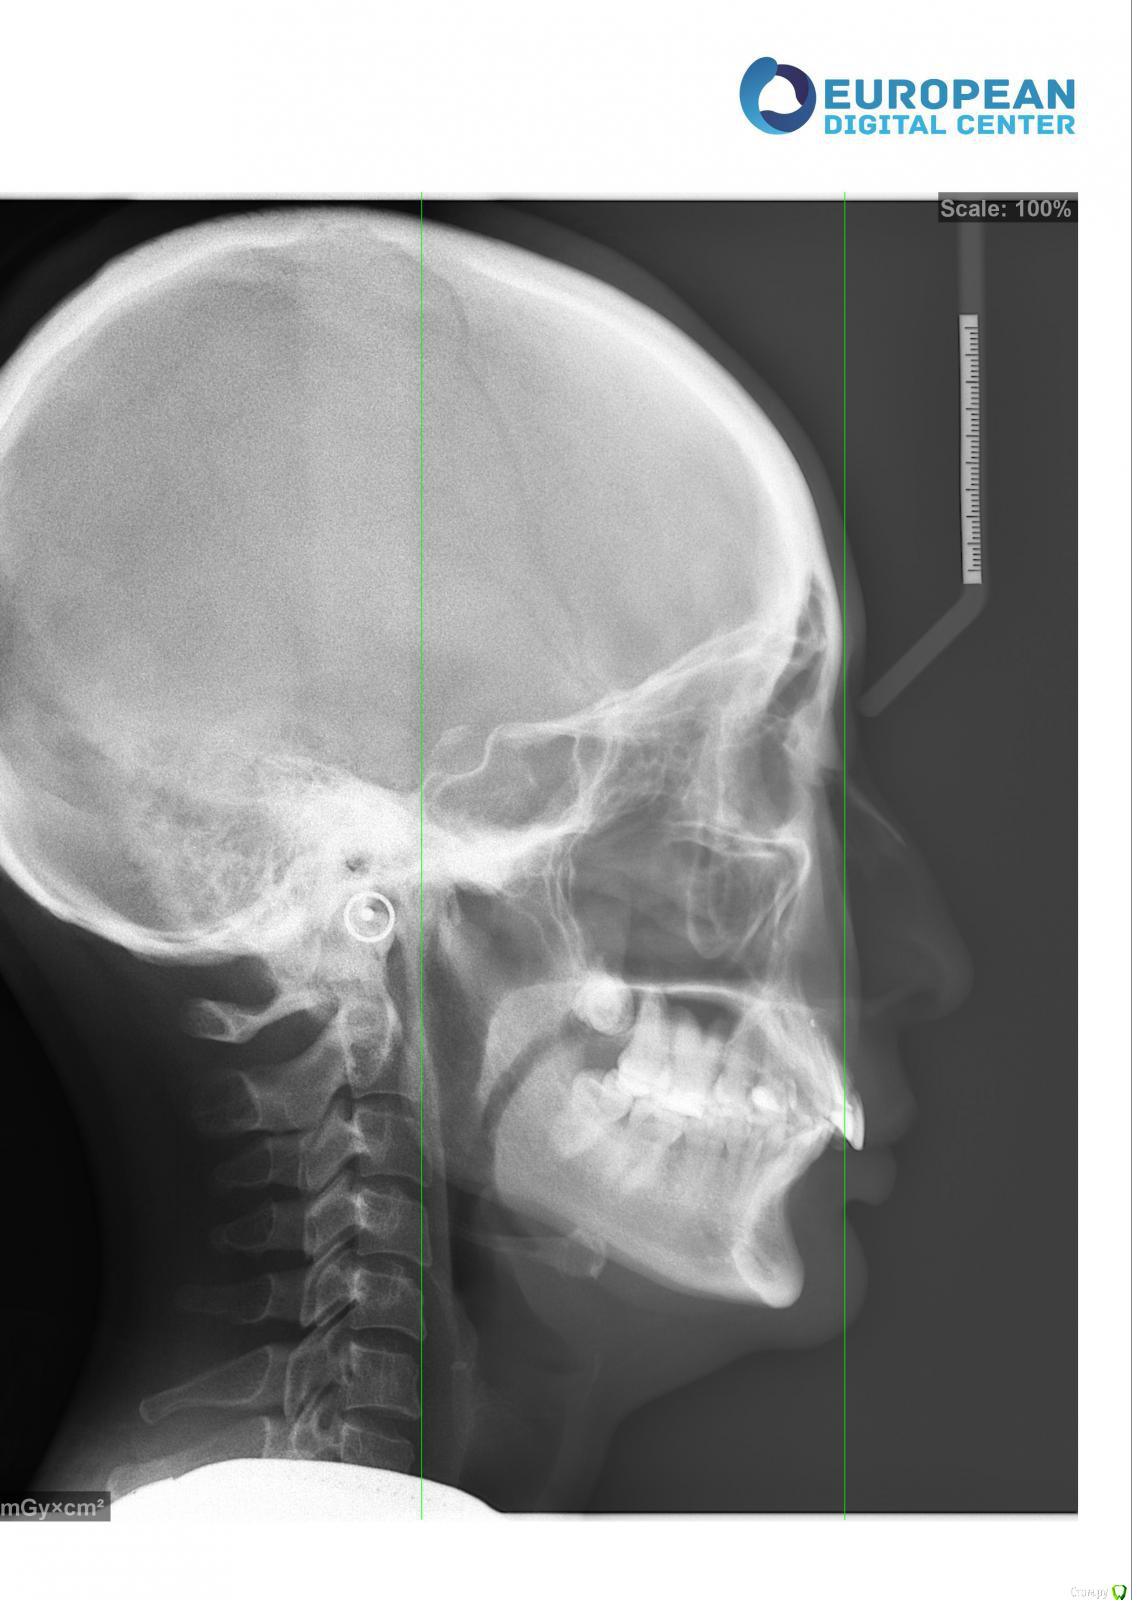

Kema Опубликовано 24 сентября, 2018 Поделиться Опубликовано 24 сентября, 2018 Здравствуйте, уважаемые профессионалы. Подскажите пожалуйста, нужна ли мне ортогнатическая операция? Ссылка на комментарий

Kema Опубликовано 25 сентября, 2018 Автор Поделиться Опубликовано 25 сентября, 2018 Хочу улучшить эстетический вид.Лет 15 назад носила брекеты только на нижней челюсти. Через 1.5 года сняла так как не было результата. На верхнюю челюсть ортодонт ставить не спешил, говорил внизу надо расправить скученность. Ещё говорил, что у меня нижняя челюсть недоразвита. Ссылка на комментарий

Kema Опубликовано 25 сентября, 2018 Автор Поделиться Опубликовано 25 сентября, 2018 У меня нет нижней правой шестёрки. Правая восьмёрка подвинула семёрку, семёрка наклонилась. Левая ретинированная восьмёрка удалена. На правой стороне жевать неудобно. Ещё верхние зубы наклонились вперёд. Начитавшись про ортогнатические операции хотела узнать показана ли мне она. Ссылка на комментарий